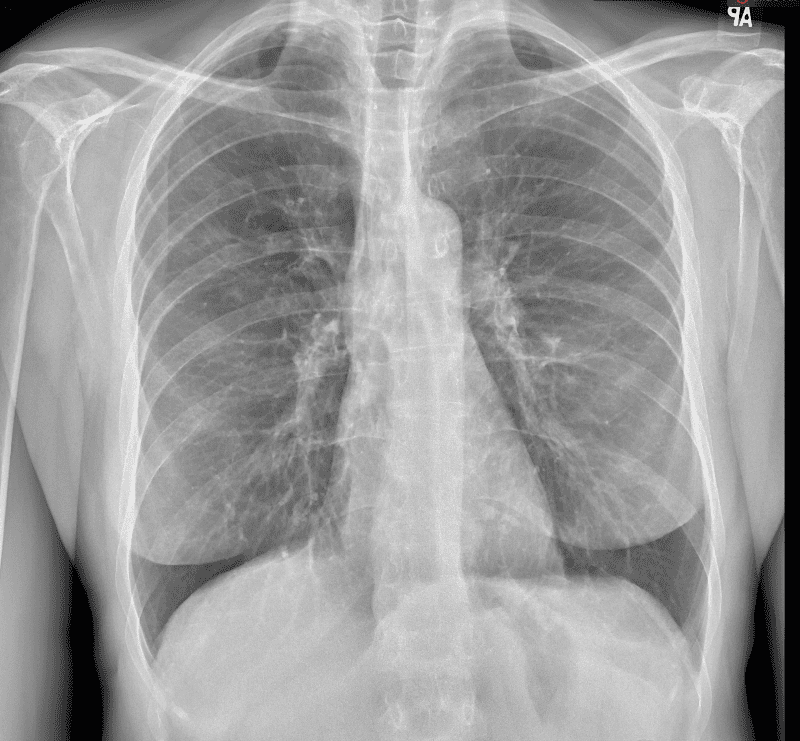

Practice Cases